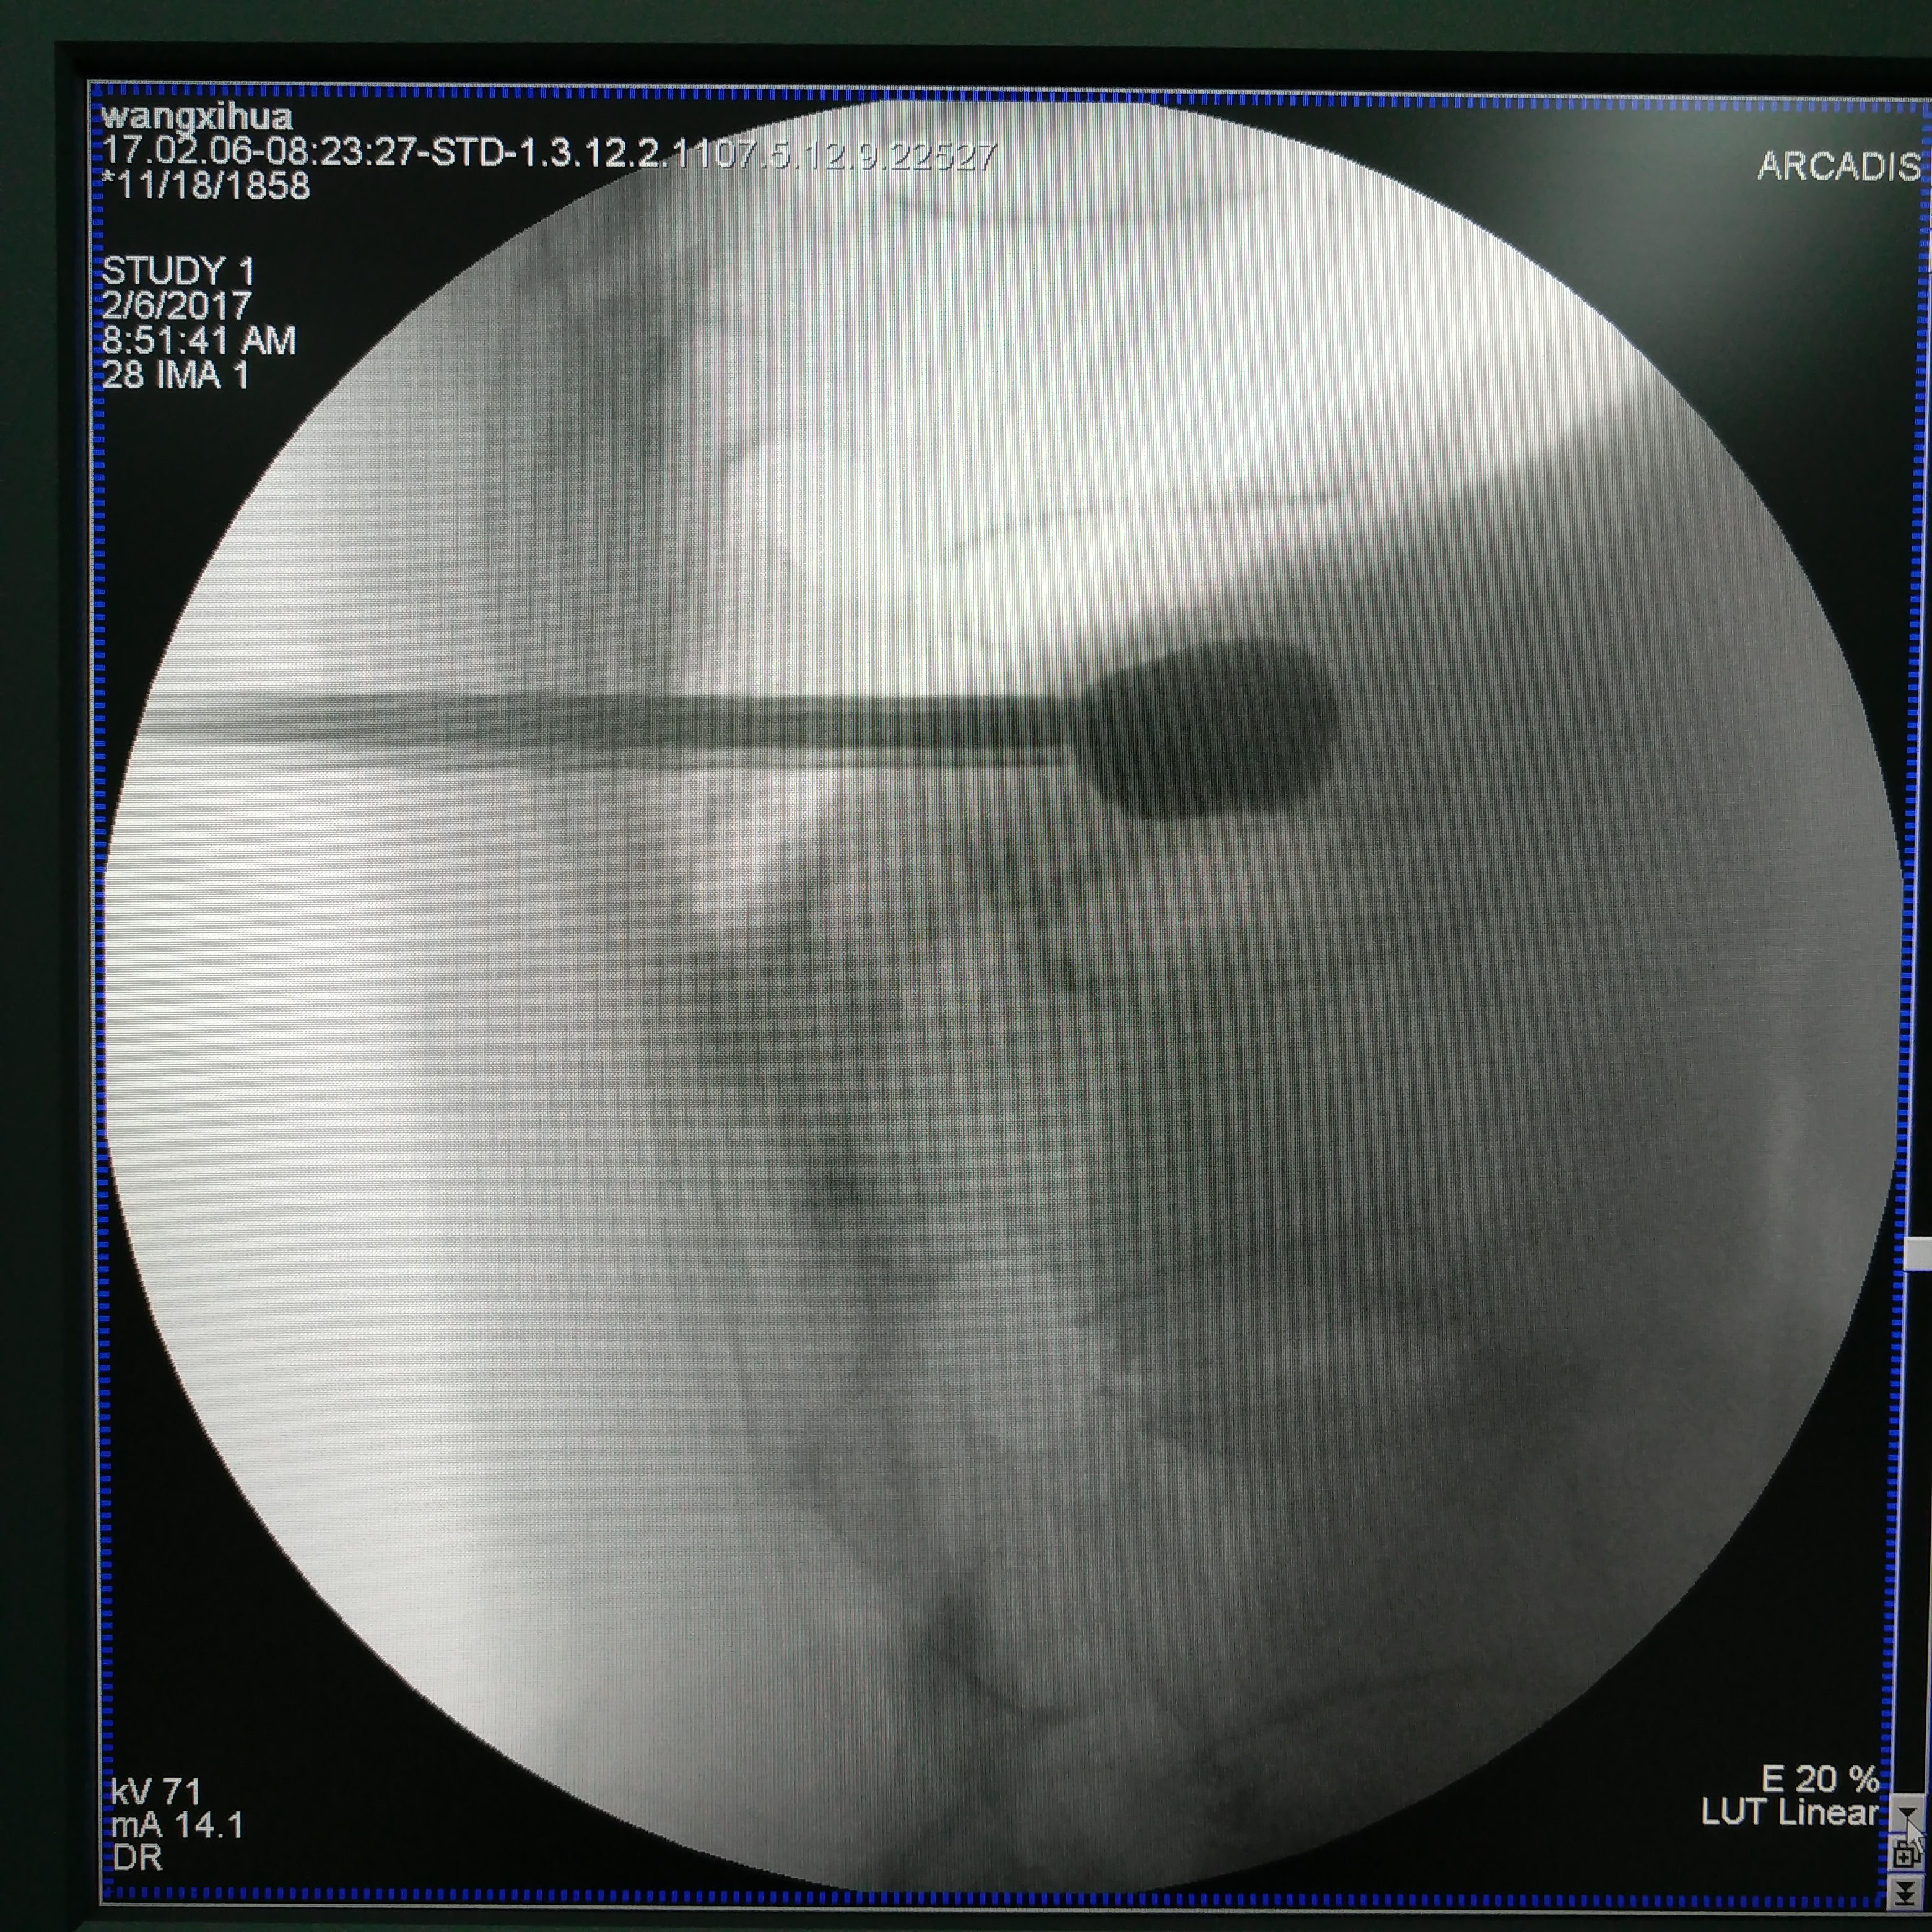

微创手术适用于老年人。骨质疏松性脊柱压缩性骨折,骨水泥填充是最好的解决办法,这是迄今为止公认的最有效的快速解决骨折疼痛的办法。近十五年来,骨质疏松性骨折的治疗得到飞速的发展,掌握这项技术的医生越来越多,为广大患者解决了痛苦,提高了生活质量,延长了寿命。

脊柱骨折球囊扩张术中